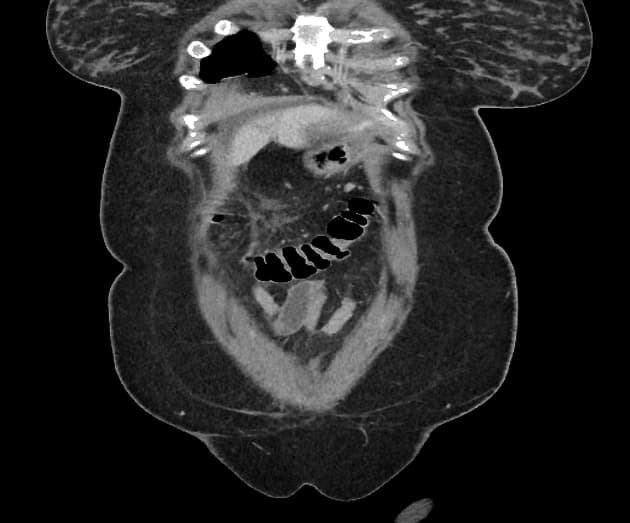

- Các nhánh đường mật trong gan (intrahepatic biliary radicles) giãn nhẹ.

- Ống mật chủ (common bile duct) giãn, thấy nhiều viên sỏi nhỏ có tín hiệu thấp ở đoạn cuối.

- Túi mật (gallbladder) căng giãn, chứa nhiều viên sỏi nhỏ.

- Tụy (pancreas) to lan tỏa và phù nề, xung quanh có dịch quanh tụy lan dọc theo các khe mỡ vùng sau phúc mạc, rõ hơn ở phía bên trái.

- Ống tụy (pancreatic duct) có vị trí, chiều dài và đường kính bình thường, cấu trúc bên trong đồng nhất, bờ trơn đều.

Sỏi túi mật (cholelithiasis) và sỏi ống mật chủ (choledocholithiasis) là những nguyên nhân phổ biến gây viêm tụy cấp (acute pancreatitis). Trong trường hợp này, viêm tụy cấp được phát hiện trên hình ảnh cộng hưởng từ đường mật tụy (MRCP) được thực hiện do có triệu chứng vàng da tắc mật và đau vùng thượng vị.

Viêm tụy cấp là một tình trạng lâm sàng phổ biến, thường do sỏi mật gây ra, đặc biệt khi chúng làm tắc ống mật chủ tại nhú tá lớn (ampulla of Vater). Trường hợp này cho thấy các hình ảnh điển hình trên MRCP bao gồm to toàn bộ tụy, dịch quanh tụy và dấu hiệu tắc nghẽn đường mật do sỏi ống mật chủ. Sự hiện diện của nhiều viên sỏi nhỏ ở đoạn cuối ống mật chủ xác nhận nguyên nhân bệnh. Chẩn đoán sớm bằng MRCP cho phép xử trí kịp thời, bao gồm nội soi mật tụy ngược dòng (ERCP) để lấy sỏi. Việc phân biệt viêm tụy cấp với các nguyên nhân khác gây đau bụng và vàng da như viêm đường mật hay ung thư tụy là rất quan trọng vì các bệnh này đòi hỏi can thiệp khác nhau.